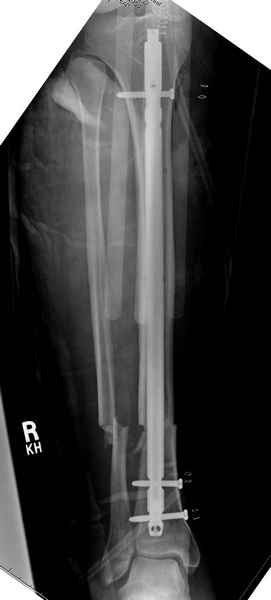

Больному с политравмой установлен наружный "spanning-bridging" фиксатор, после нескольких Irrigation&Debridment на фоне отрицательного посева из раны, через открытый участок установлен 4.5 mm Locking Plate.

На фоне фиксированного перелома бедра мероприятия по восстановлению мягкотканого покрова. Перелом голени зафиксирован после стабилизации бедра традиционным методом.

Имя     : 6 open femur, tibia exfix 3.jpg

Тип     : image/jpeg

Размер  : 44616 байтов